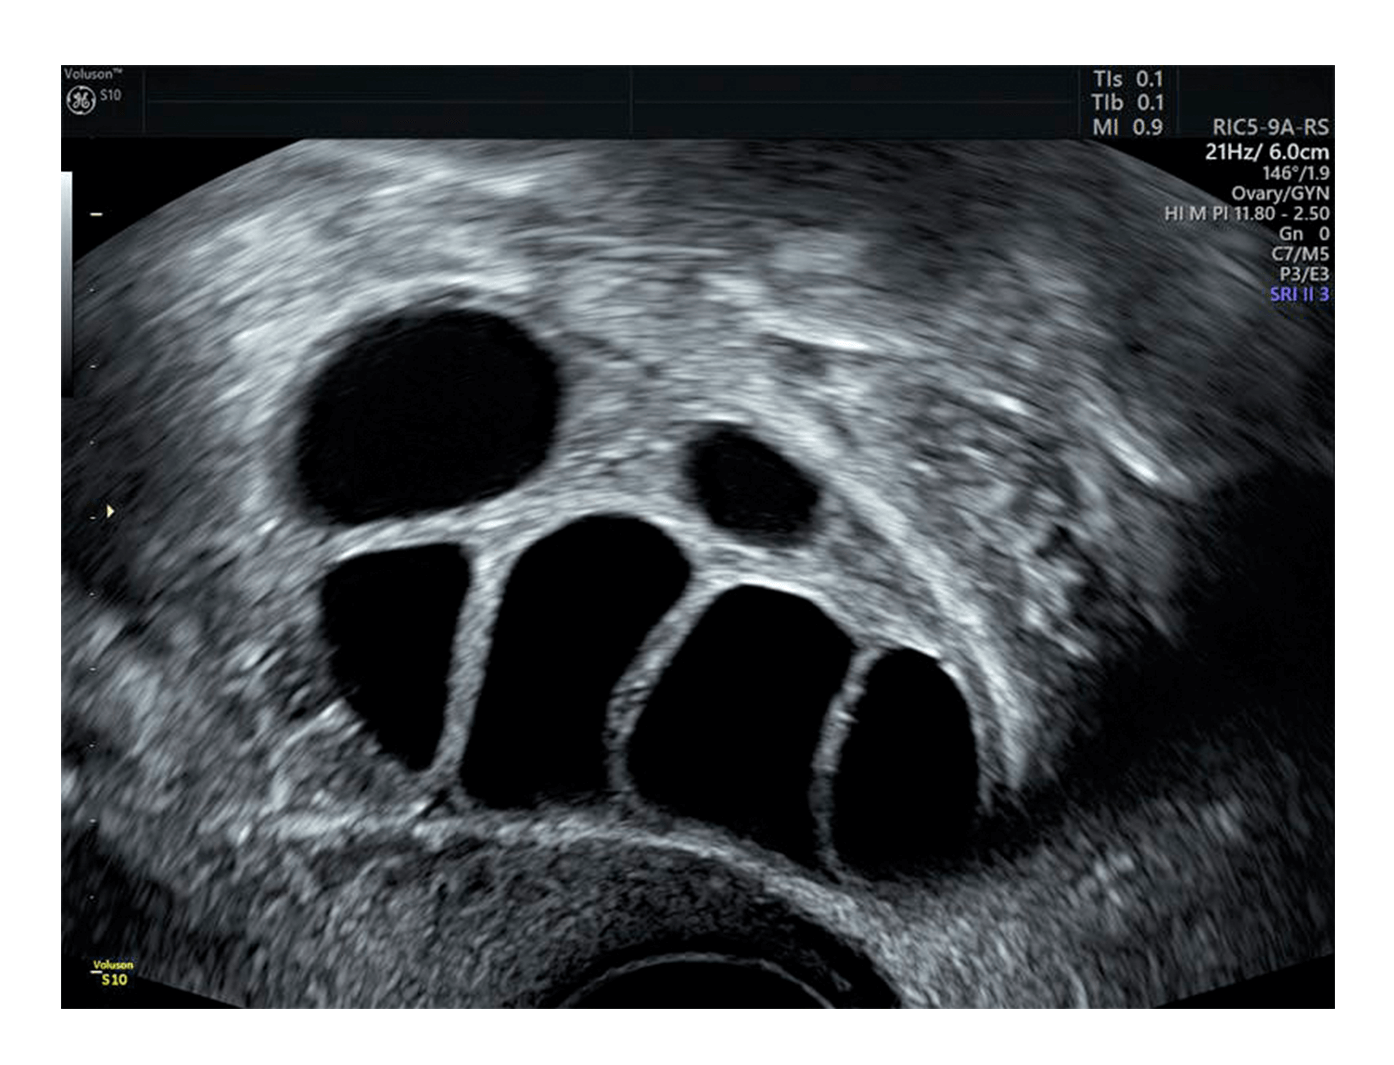

Es simple matemática: cuanto más número de óvulos de calidad tiene la mujer, mayor será su oportunidad de tener un bebé. Esto es porque las medidas foliculares precisas durante la estimulación son críticas en el proceso de FIV. Estos cálculos dictan el momento y folículos perdidos podrían significar oportunidades perdidas.

Para reducir posibles errores, Palumbo se basa en el SonoAVCfollicle de Voluson™, una herramienta de ultrasonido que mide automáticamente los folículos usando tecnología 3D. Simplemente seleccione un ovario y escanee. En la mayoría de los casos no es necesario contar manualmente.

El SonoAVCfollicle también está diseñado para superar otros desafíos, incluyendo la variabilidad de inter observadores e intra observadores. De hecho, se ha demostrado que el ultrasonido 3D aumenta La reproducibilidad de la medición y la evalualuación.1,2 También permite la estandarización de exámenes de ultrasonido a través del enfoque multiplanar automatizado.3,4

“Con los volúmenes tenemos una imagen más precisa de todo el ovario y podemos optimizar el número de óvulos maduros que obtenemos”, dijo Palumbo, Por ejemplo, en personas que responden mal sabemos que cada folículo es importante. Si observamos las mediciones manuales continuaríamos la estimulación, pero muchas veces SonoAVCfollicle nos dice que paremos, la paciente está lista”.